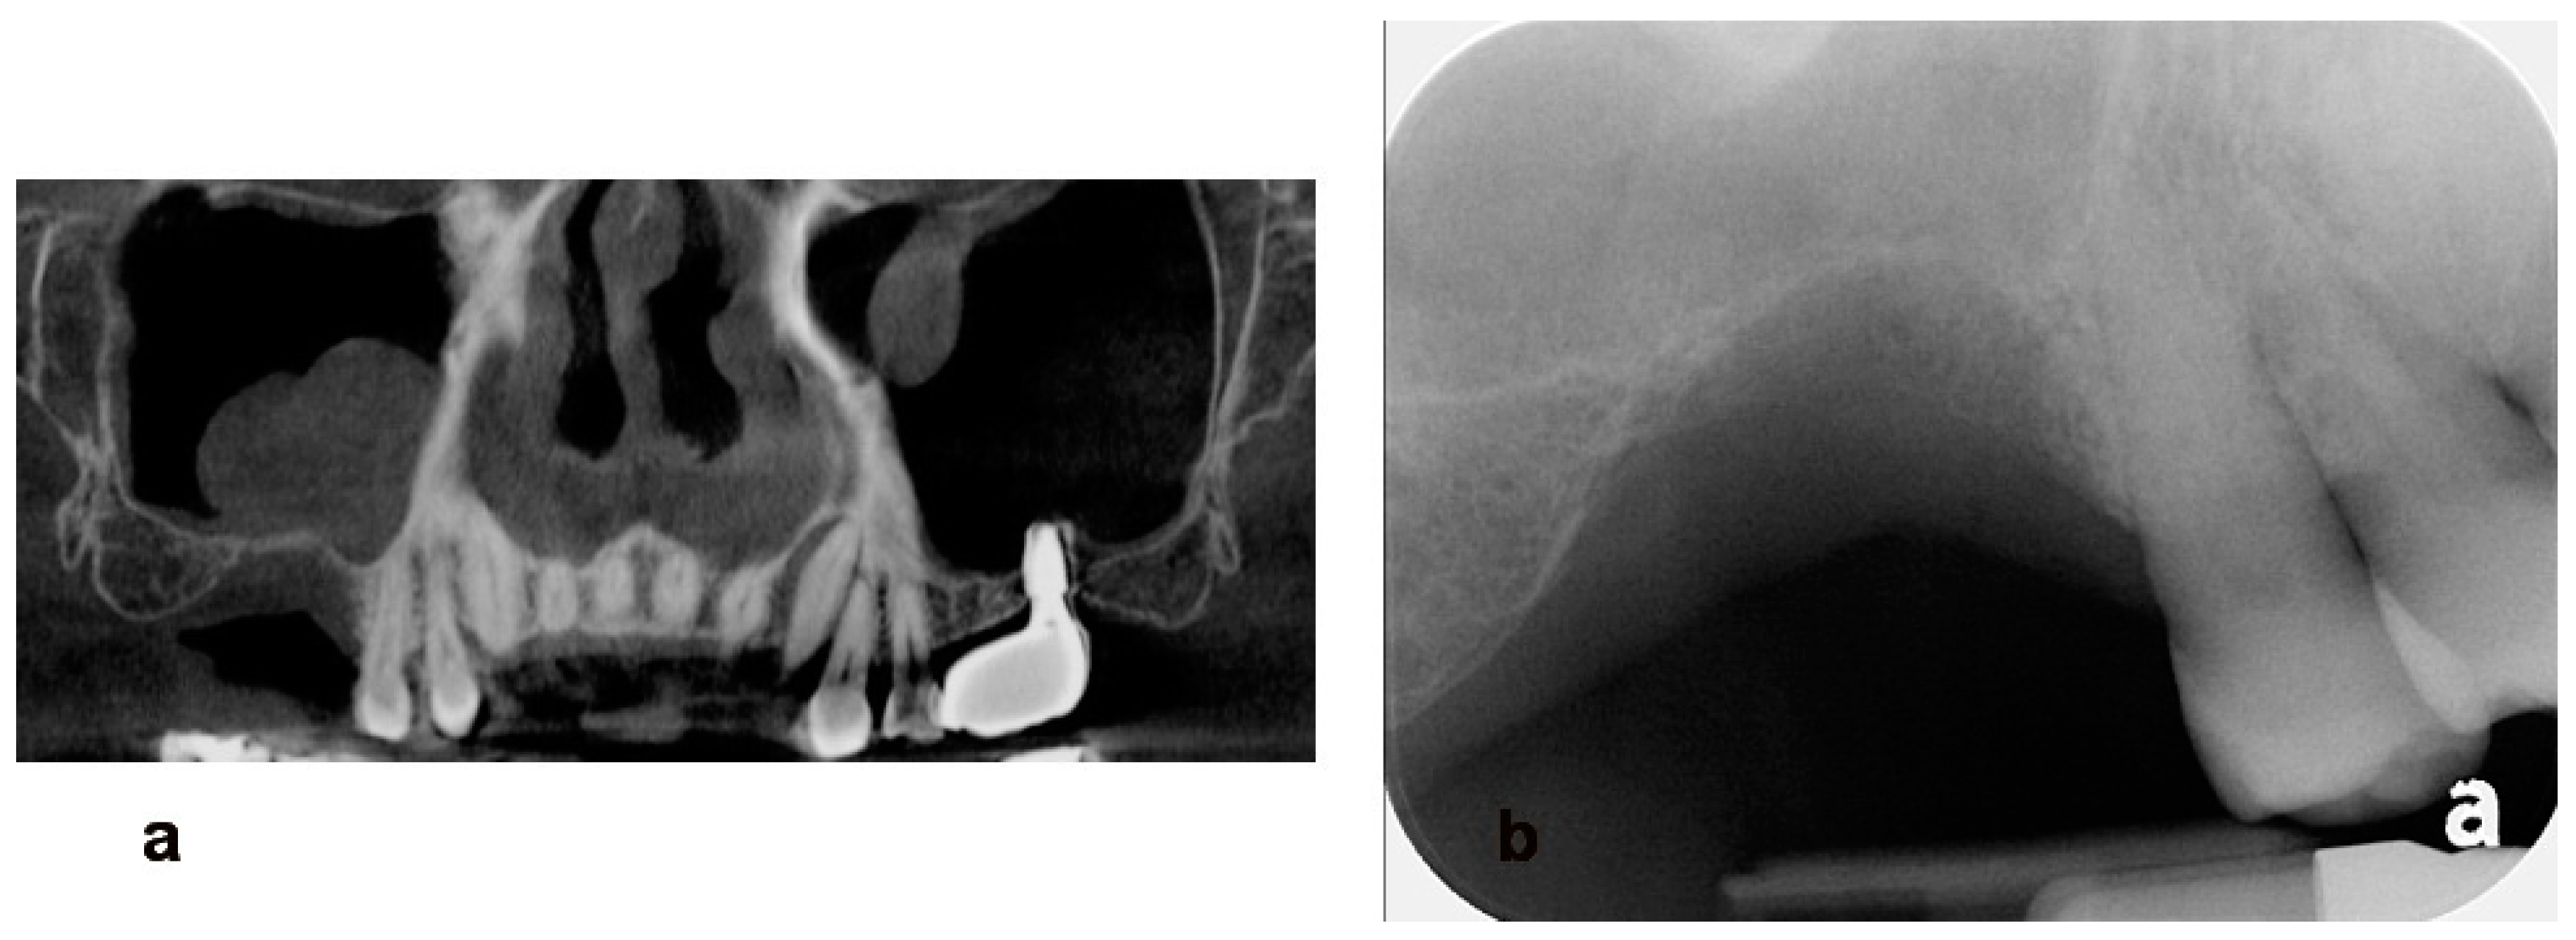

Utilization of Tenting Pole Abutments for the Reconstruction of Severely Resorbed Alveolar Bone: Technical Considerations and Case Series Reports

2. Case Presentations